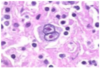

Qual é o nome dessa célula característica do Linfoma de Hodgkin?

Células de Reed Stemberg

Qual é o linfoma originado pela proliferação clonal de linfócitos B do centro germinativo, caracterizado pela presença de células de Reed-Stemberg?

As células de Reed-Stemberg, apesar de serem muito sugestivas de LH, também podem ser encontradas em quais situações?

Linfomas não Hodgkin, mononucleose infecciosa, carcinomas e sarcomas